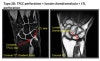

치료방법이 다양한데 봉합 내지는 debridement를 절제하는 관절경 수술을 고려할 수 있습니다.

* Central : Poor vascularized(Healing potential minimal)

Arthroscopic debridement up to 2/3 of articular disc